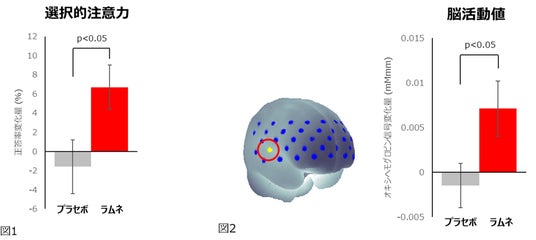

ラムネ摂取時はプラセボ摂取時と比較して、選択的注意力の指標であるフランカー課題の正答率が有意に上昇(図1)し、その時の脳血流(オキシヘモグロビン信号)が有意に増大(図2)しました。また、EACLの「エネルギー覚醒+」スコア(図3)とPOMS2短縮版の「活気‐活力」スコア(図4)が有意に上昇し、反対にネガティブ気分尺度である「怒り‐敵意」とTMDスコアが有意に低下しました。

この結果から、ラムネを摂取することによって認知テストにポジティブな気分で集中して取り組み、脳の一部の機能の活動が活性化することが示唆されました。本研究では集中して認知テストに取組んでいる時に脳の一部の活動が活性化していることを現象として捉えることができましたが、それらの関連性やメカニズムについては未解明な点も多く、今後の更なる研究が望まれます。